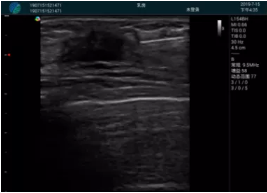

腺體內(nèi)部清晰顯示一低回聲塊影,形態(tài)不規(guī)則,邊界模糊,邊緣呈毛刺狀,內(nèi)部見砂礫樣鈣化

M20引導(dǎo)下穿刺活檢術(shù)

M20引導(dǎo)下平面內(nèi)穿刺取出的腫塊組織

M20查看:囊內(nèi)回聲均勻,邊界清晰,囊壁光滑

M20引導(dǎo)抽吸術(shù)后囊腫消失,原區(qū)域空腔形成,脂肪層與腺體層架構(gòu)發(fā)生改變